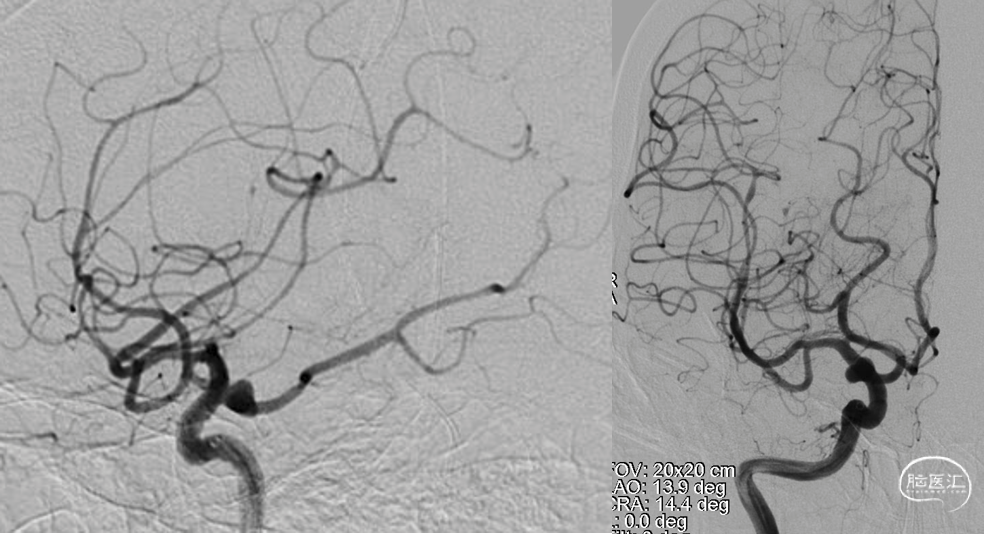

DSA

平均宽度(4.5+3.8)=4.2mm,最小深度7.5mm,选择SL5x3

微导管到位动脉瘤腔

通过VIA17释放web

造影可见造影剂滞留

手推造影-推挤-造影

解脱web

术后正侧位造影

术后CBCT